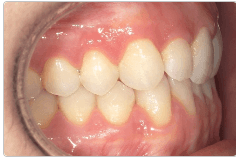

Diganosis: Moderate lower anterior crowding, square and narrow maxilla, rotated #19

Adjuncts: Attachments

Initial treatment

INTRAORAL